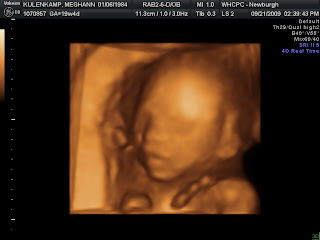

The tech was able to get all of the measurements that she was needing for the entire Anatomy Scan.  Baby K weighs 13 oz right now with a nice strong heartbeat of 142 bpm.  I found out that I gained 5 more lbs in the last 4 weeks making a total of 6 lbs.  I have really popped out again the last week and a half. I know, I need to post some progress pictures.  If I had some, I would...but I don't.  I need to take some :)

So, as I said, Baby K was being very cooperative for the tech and she decided that she was going to take all kinds of pictures. Really wish she would have given me a few more than what she did, but oh well! Needless to say, hubby was really excited when she scanned to this...

It's a boy!!! I wish everyone could have seen hubby's face :) it was priceless.  He was grinning from ear to ear! And yes, I am super happy too! I honestly just wanted to make sure the baby is healthy and he seems to be doing really well in there!!  After the tech got all the measurements she was needing, he decided that he had enough and started kicking up a storm :)

I have definitely been able to feel him a lot more within the past few days. He is getting stronger by the day. He really starts to get wound up when I lay down to go to sleep (of course) and after I have a full belly. So, here is one more shot of his cute little profile! Oh yea, and I am now at the 20 week mark!!